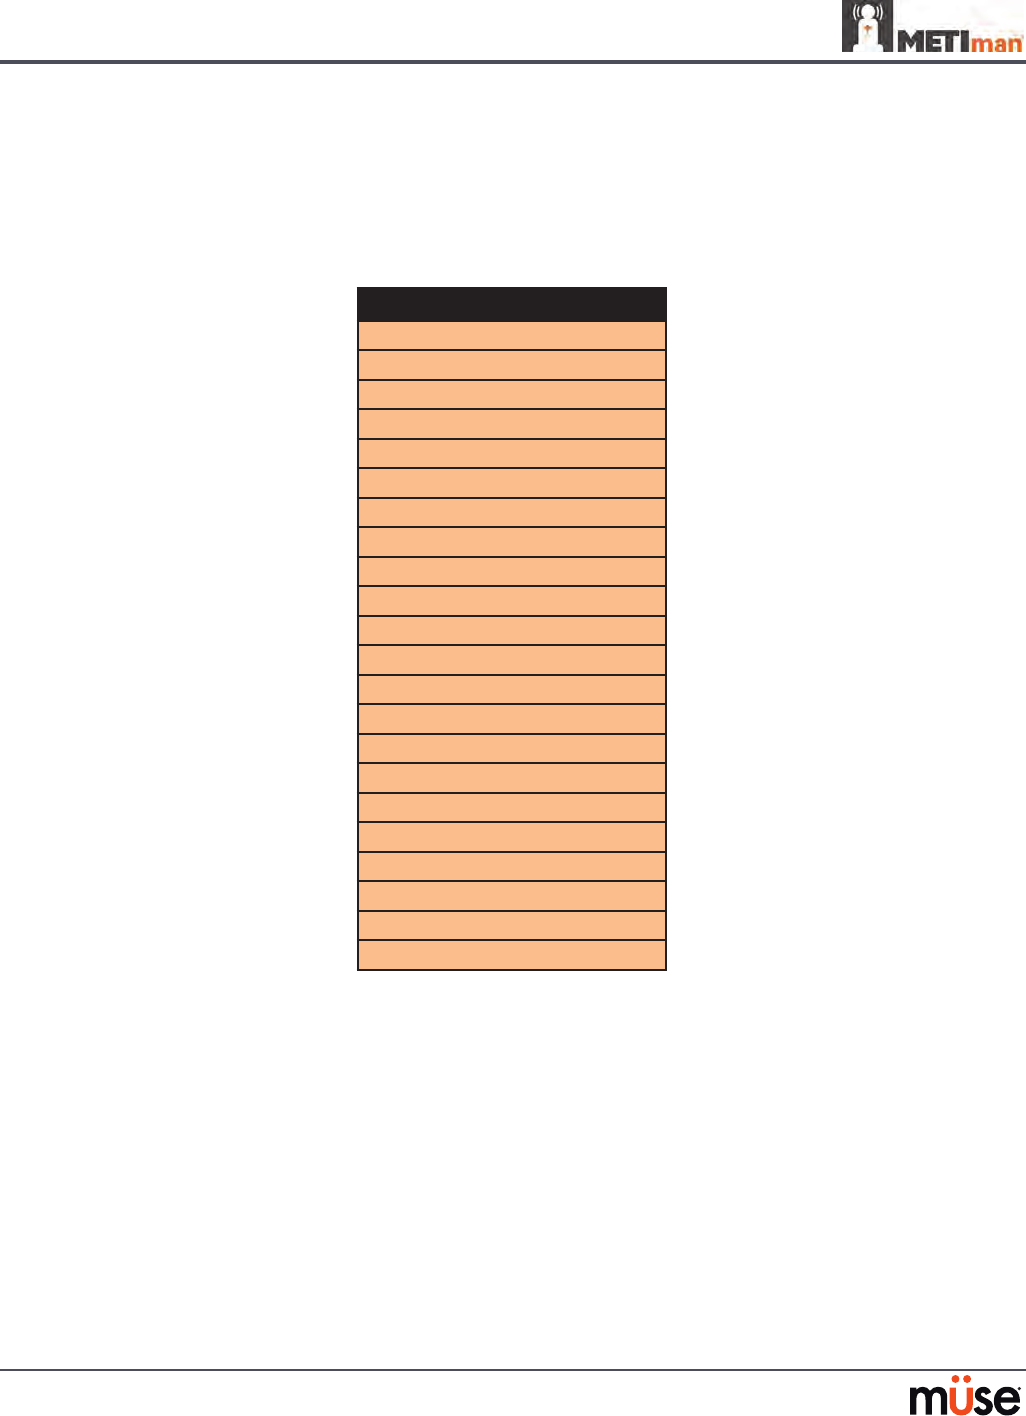

Airway Features

Anatomy, Physiology

and Clinical Signs Clinical Interventions, Patient

Monitoring and Scenarios. Software Control Manual

Control

Realistic Upper

Airway (Oropharynx,

Nasopharynx and Larynx)

(Prehospital only)

Allows direct laryngoscopy, oral and

nasal intubation and use of specialty

airway devices. Simulator detects

and responds appropriately to right

mainstem intubation. Endobronchial

intubation results in unilateral chest

excursion and breath sounds.

None required. None required.

Trachea, Left and Right

Mainstem Bronchi

(Prehospital only)

Tracheal intubation results in bilateral

chest excursion and breath sounds. None required. None required.

Airway Management and

Ventilation

Alveolar and arterial gas concentrations

appropriately reect the ecacy of

ventilation and oxygen administration.

Oxygen

administration input

by the instructor.

VIEW: Respiratory

None required.

Gastric Distention

(Prehospital only)

Esophageal intubation results in gastric

distension and the absence of breath

sounds, chest excursion and CO2 output.

None required. None required.

Breakaway Teeth

(Prehospital only)

Upper front teeth can be dislodged if

laryngoscopy is performed incorrectly. None required. See Breakaway

Teeth

Tongue Edema

(On/O)

Hinders, but does not prevent,

intubation. VIEW: Respiratory None required.

Posterior Pharynx

Swelling

(Prehospital only)

Obstructs view of larynx to prevent

intubation, but allows mask ventilation

“can’t intubate, can ventilate” scenario.

VIEW: Respiratory None required.

Laryngospasm

(Prehospital only)

Closes vocal cords and prevents

intubation and ventilation. When used

with posterior pharynx swelling, creates

a “can’t intubate, can’t ventilate” scenario.

VIEW: Respiratory None required.

Cricothyroid Membrane Allows needle cricothyrotomy,

transtracheal jet ventilation, retrograde

wire techniques and cricothyrotomy.

None required. See

Cricothyrotomy,

132